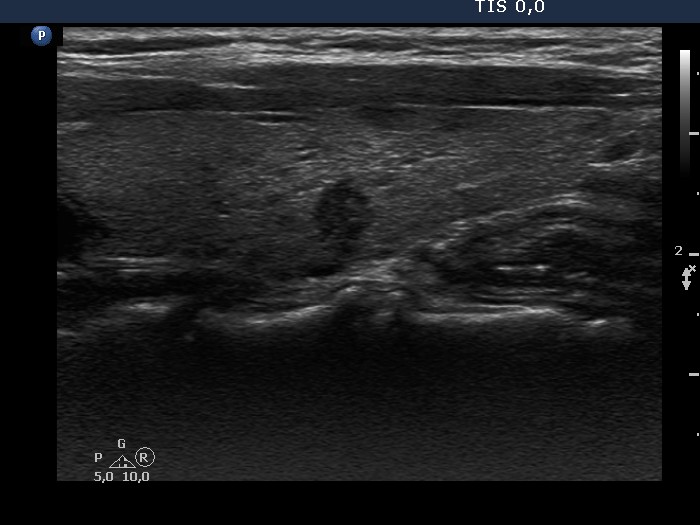

Benign nodular goiter (cytology) - case 2104

There is a small, less hypoechogenic part in the ventral surface of the nodule (yellow arrow). The echogenicity of this part is identical to that of the muscle fiber running on the ventral border of the thyroid (red arrow). Because the nodule is located in the ventral part of the lobe, these different tissues with identical echogenicity are in contact with each other, which causes a non-pathological blur. On the other hand, the nodule presents pathological blur, as well, this is marked with green arrows.